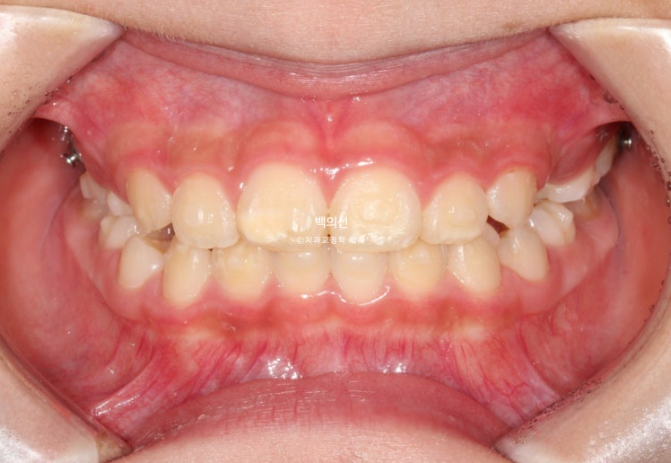

24년 10월부터 25년 3월까지, 16개 추가장치를 다 낀 후 모습입니다.

25.03

턱의 위치는 6개월간 자연스럽게 잘 유지가 되었고 치료를 마무리 합니다.

중심선도 아주 잘 맞습니다.

교합은 좋고 이제 막 첫번째 작은어금니가 맹출중입니다.